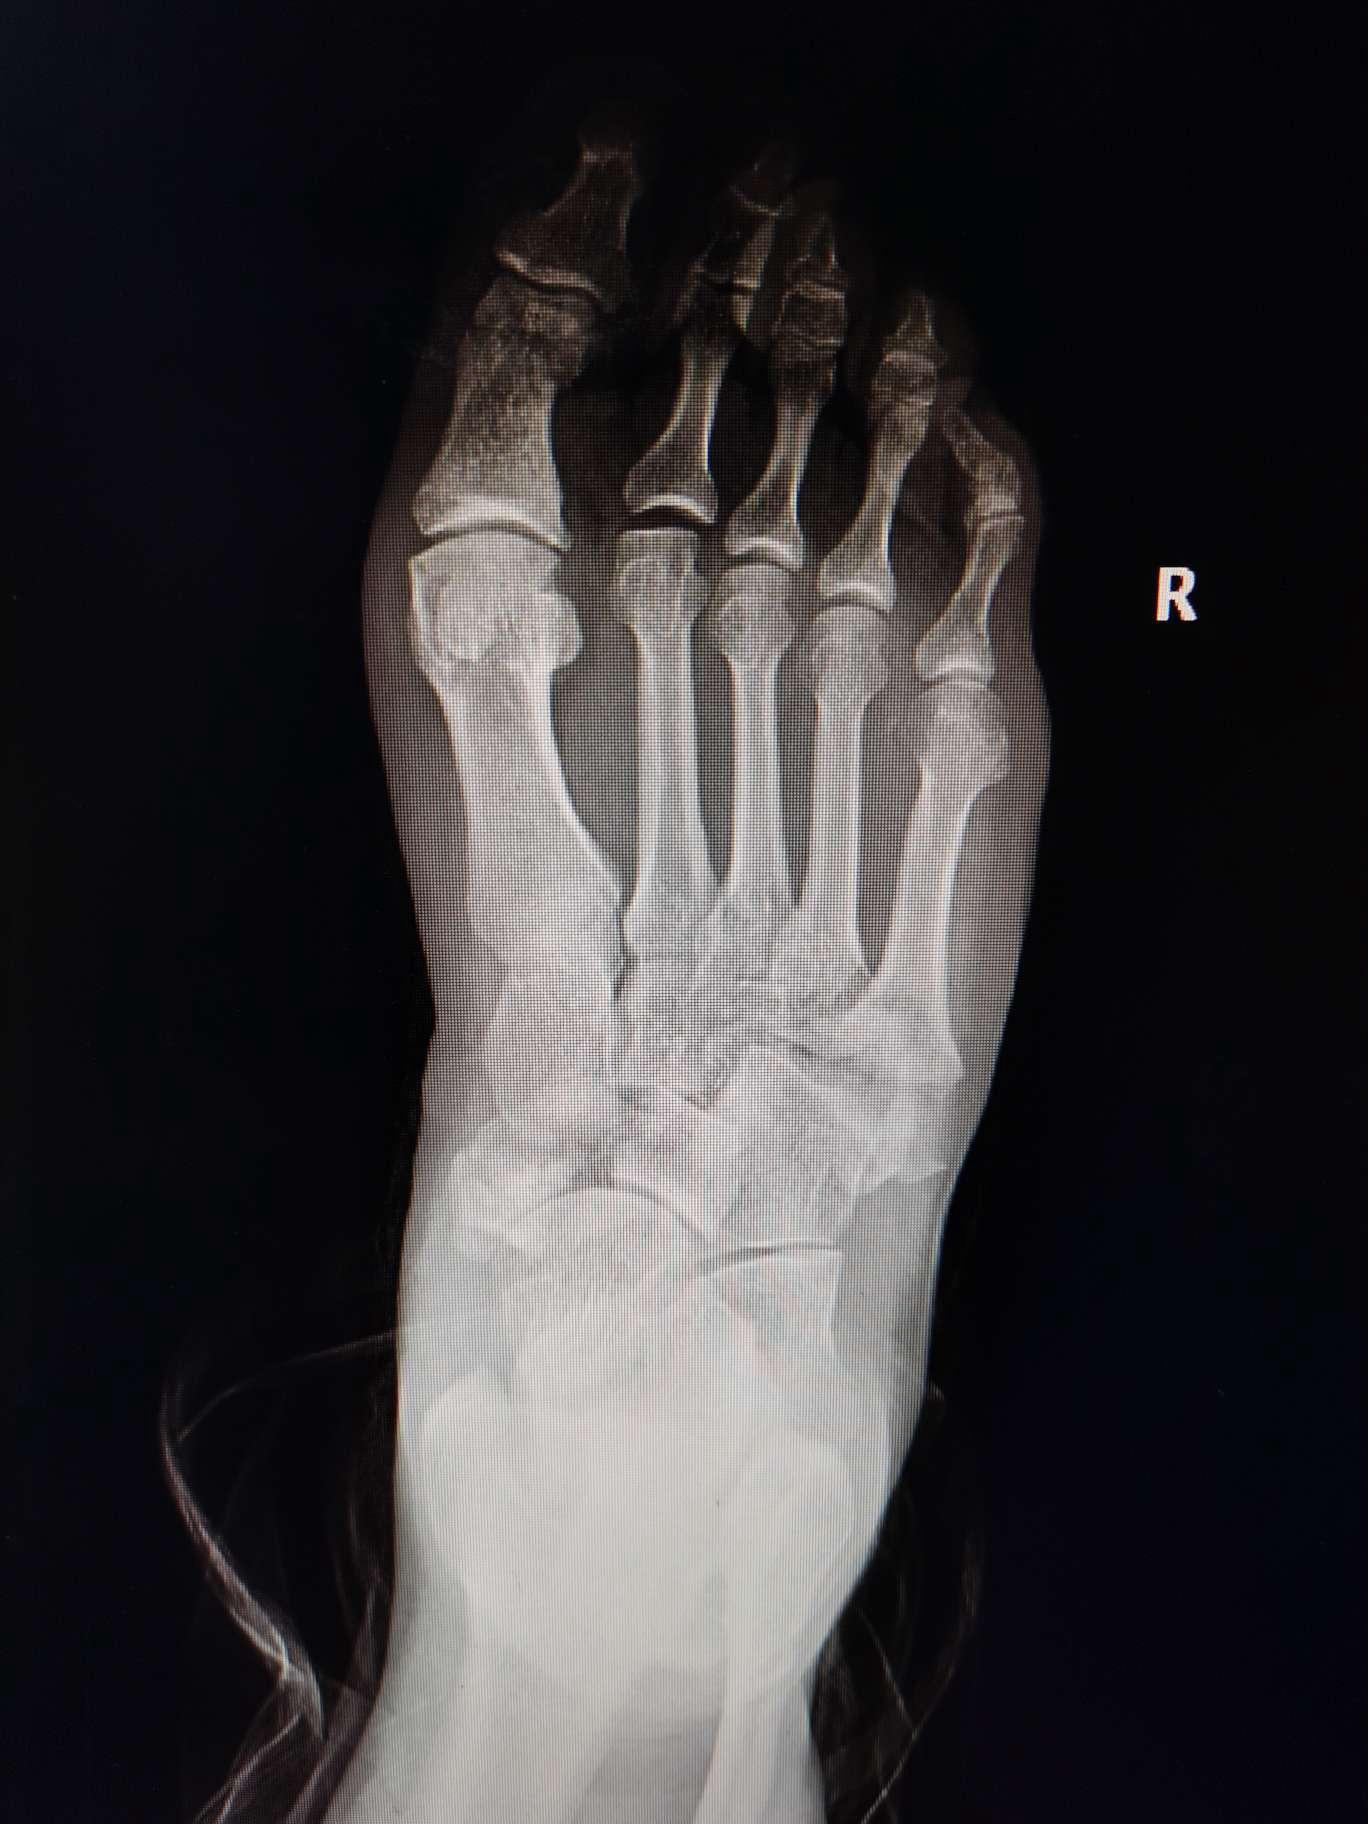

一例足舟骨第五跖骨基底粉碎性骨折的治疗

右脚骨折

右足第3,4,5趾骨骨折